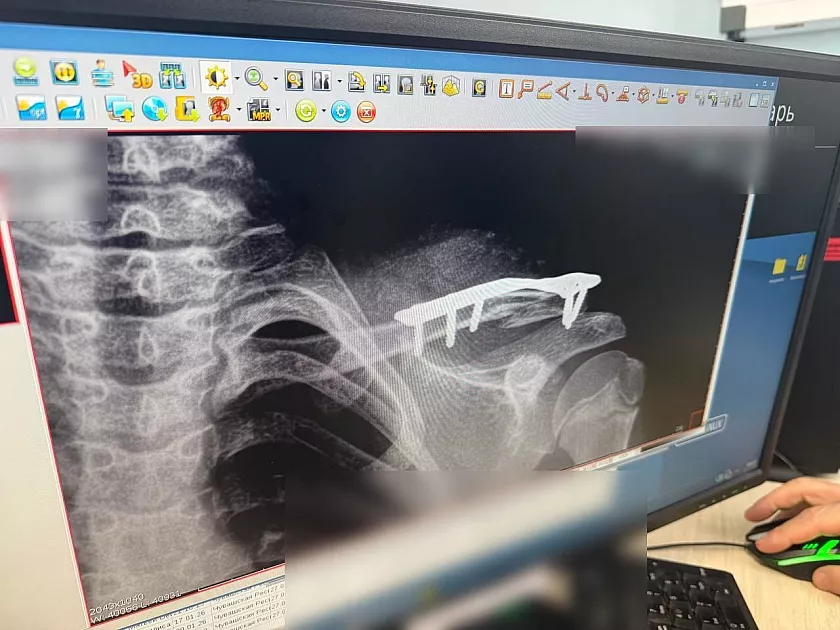

По словам заведующего травматологическим отделением Игоря Ластухина, дети получают переломы конечностей и позвоночника, часто катаются в неположенных местах, вдвоем или втроем на одной ватрушке и без присмотра родителей. Одиннадцатилетняя девочка из Новочебоксарска получила компрессионный перелом трех поясничных позвонков, а мальчик того же возраста – перелом ключицы после столкновения с другим ребенком.

Фото Минздрава Чувашии